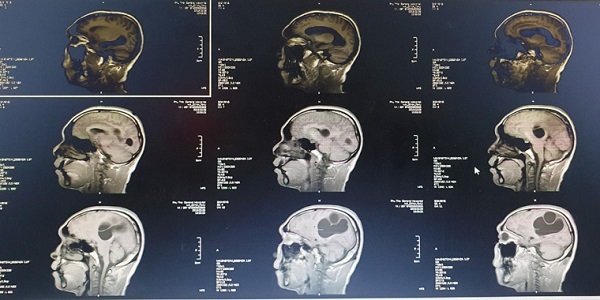

Thanh niên 18 tuổi đến khám trong tình trạng bị đau đầu, nôn mửa và co giật. Kiểm tra, bác sĩ giật mình phát hiện toàn bộ cơ thể bệnh nhân bị sán dây bao phủ, rất đáng sợ

Ngày 21/3, thông tin từ BV Đa khoa tỉnh Phú Thọ cho biết, Khoa Ngoại thần kinh của BV vừa tiếp nhận trường hợp nam bệnh nhân có ổ sán não khổng lồ.

Khi phẫu thuật mở hộp sọ, các bác sĩ tá hỏa khi phát hiện hơn 30 trứng sán dây trong đầu bệnh nhân.